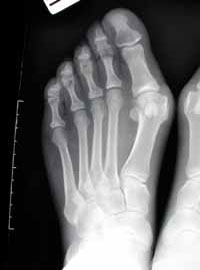

CHIRURGIA DEL PIEDE: diabetico, alluce valgo, dita a martello, neuroma di Morton.